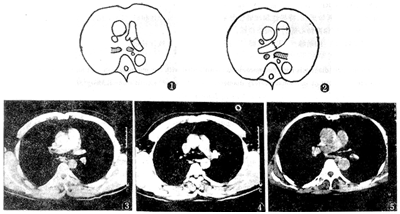

3.测量指标包括:(1)主肺动脉直径(MPA);(2)右肺动脉直径(RPA);(3)左肺动脉直径(LPA)。选择左肺动脉层面和右肺动脉层面图像,测量肺动脉干中部与左右肺动脉分叉处最大直径。MPA及其分支的测量见图1、图2。按不同组别计算平均值和标准差,各组间测量结果使用t检验作统计学处理。

图1 左肺动脉层面测量LPA 图2 右肺动脉层面测量MPA和RPA 图3、 图4 正常人MPA、RPA和LPA 图5 Ⅰ期煤工尘肺,MPA和RPA正常 图6、 图7 Ⅱ期煤工尘肺合并肺心病,MPA和RPA显著增宽,LPA正常 图8 Ⅲ期煤工尘肺合并肺结核,MPA增宽,RPA正常

Fig 1 LPA layer measurement of left pulmonary artery Fig 2 MPA and RPA layer measurement of right pulmonary artery Fig 3,4 Healthy people's MPA,RPA and LPA Fig 5 Stage Ⅰ coal pneumoconiosis,the MPA and RPA are normal Fig 6,7 Stage Ⅱ coal pneumoconiosis complicated with cor pulmonale,the MPA and RPA are wider obviously,but LPA normal Fig 8 Stage Ⅲ coal pneumoconiosis complicated with TB,the MPA are wider,but RPA normal